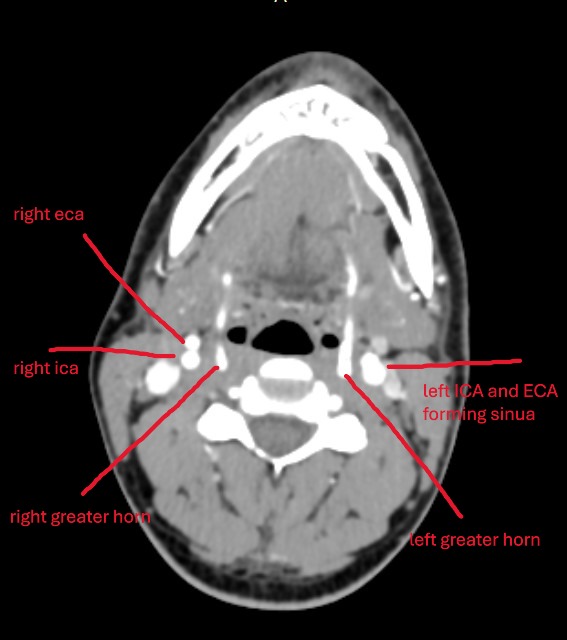

Also @madhavshrma if you post this axial view of your hyoid bone greater horns I can see if they are digging into any arteries/veins! You might be able to see more of the hyoid in one slice than me, as mine is pretty angled. The greater horn tips are the important pieces to get in the image.

I got my scan through email…being from non medical field…how to see greter horn compressing carotid artery bulb or biefurcation…how can i send that email to u i tried to attach but unable to share size is 350 mb…can anyone share email so that u guys look into my scan i share you…i tried little bit in radiant viewer and got these images

@madhavshrma it doesn’t seem to me from these pictures that the greater horns are digging into the carotid bulb. On both sides it looks as though your carotids glide along the outside of greater horns. That’s not to say that your symptoms aren’t coming from there, I just don’t see any direct bone on carotid contact that I think would be significant in this specific position, unless the left greater horn is rubbing against say the carotid sinus nerve or carotid body, but I’m not sure at this angle. Your left greater horn does seem position lower than your left, which brings it closer to your carotid sinus.

Your right greater horn looks like type VIII as I circled in the image. Your left looks closer to type X I’d say, where the ICA and ECA are closer to form the carotid sinus.